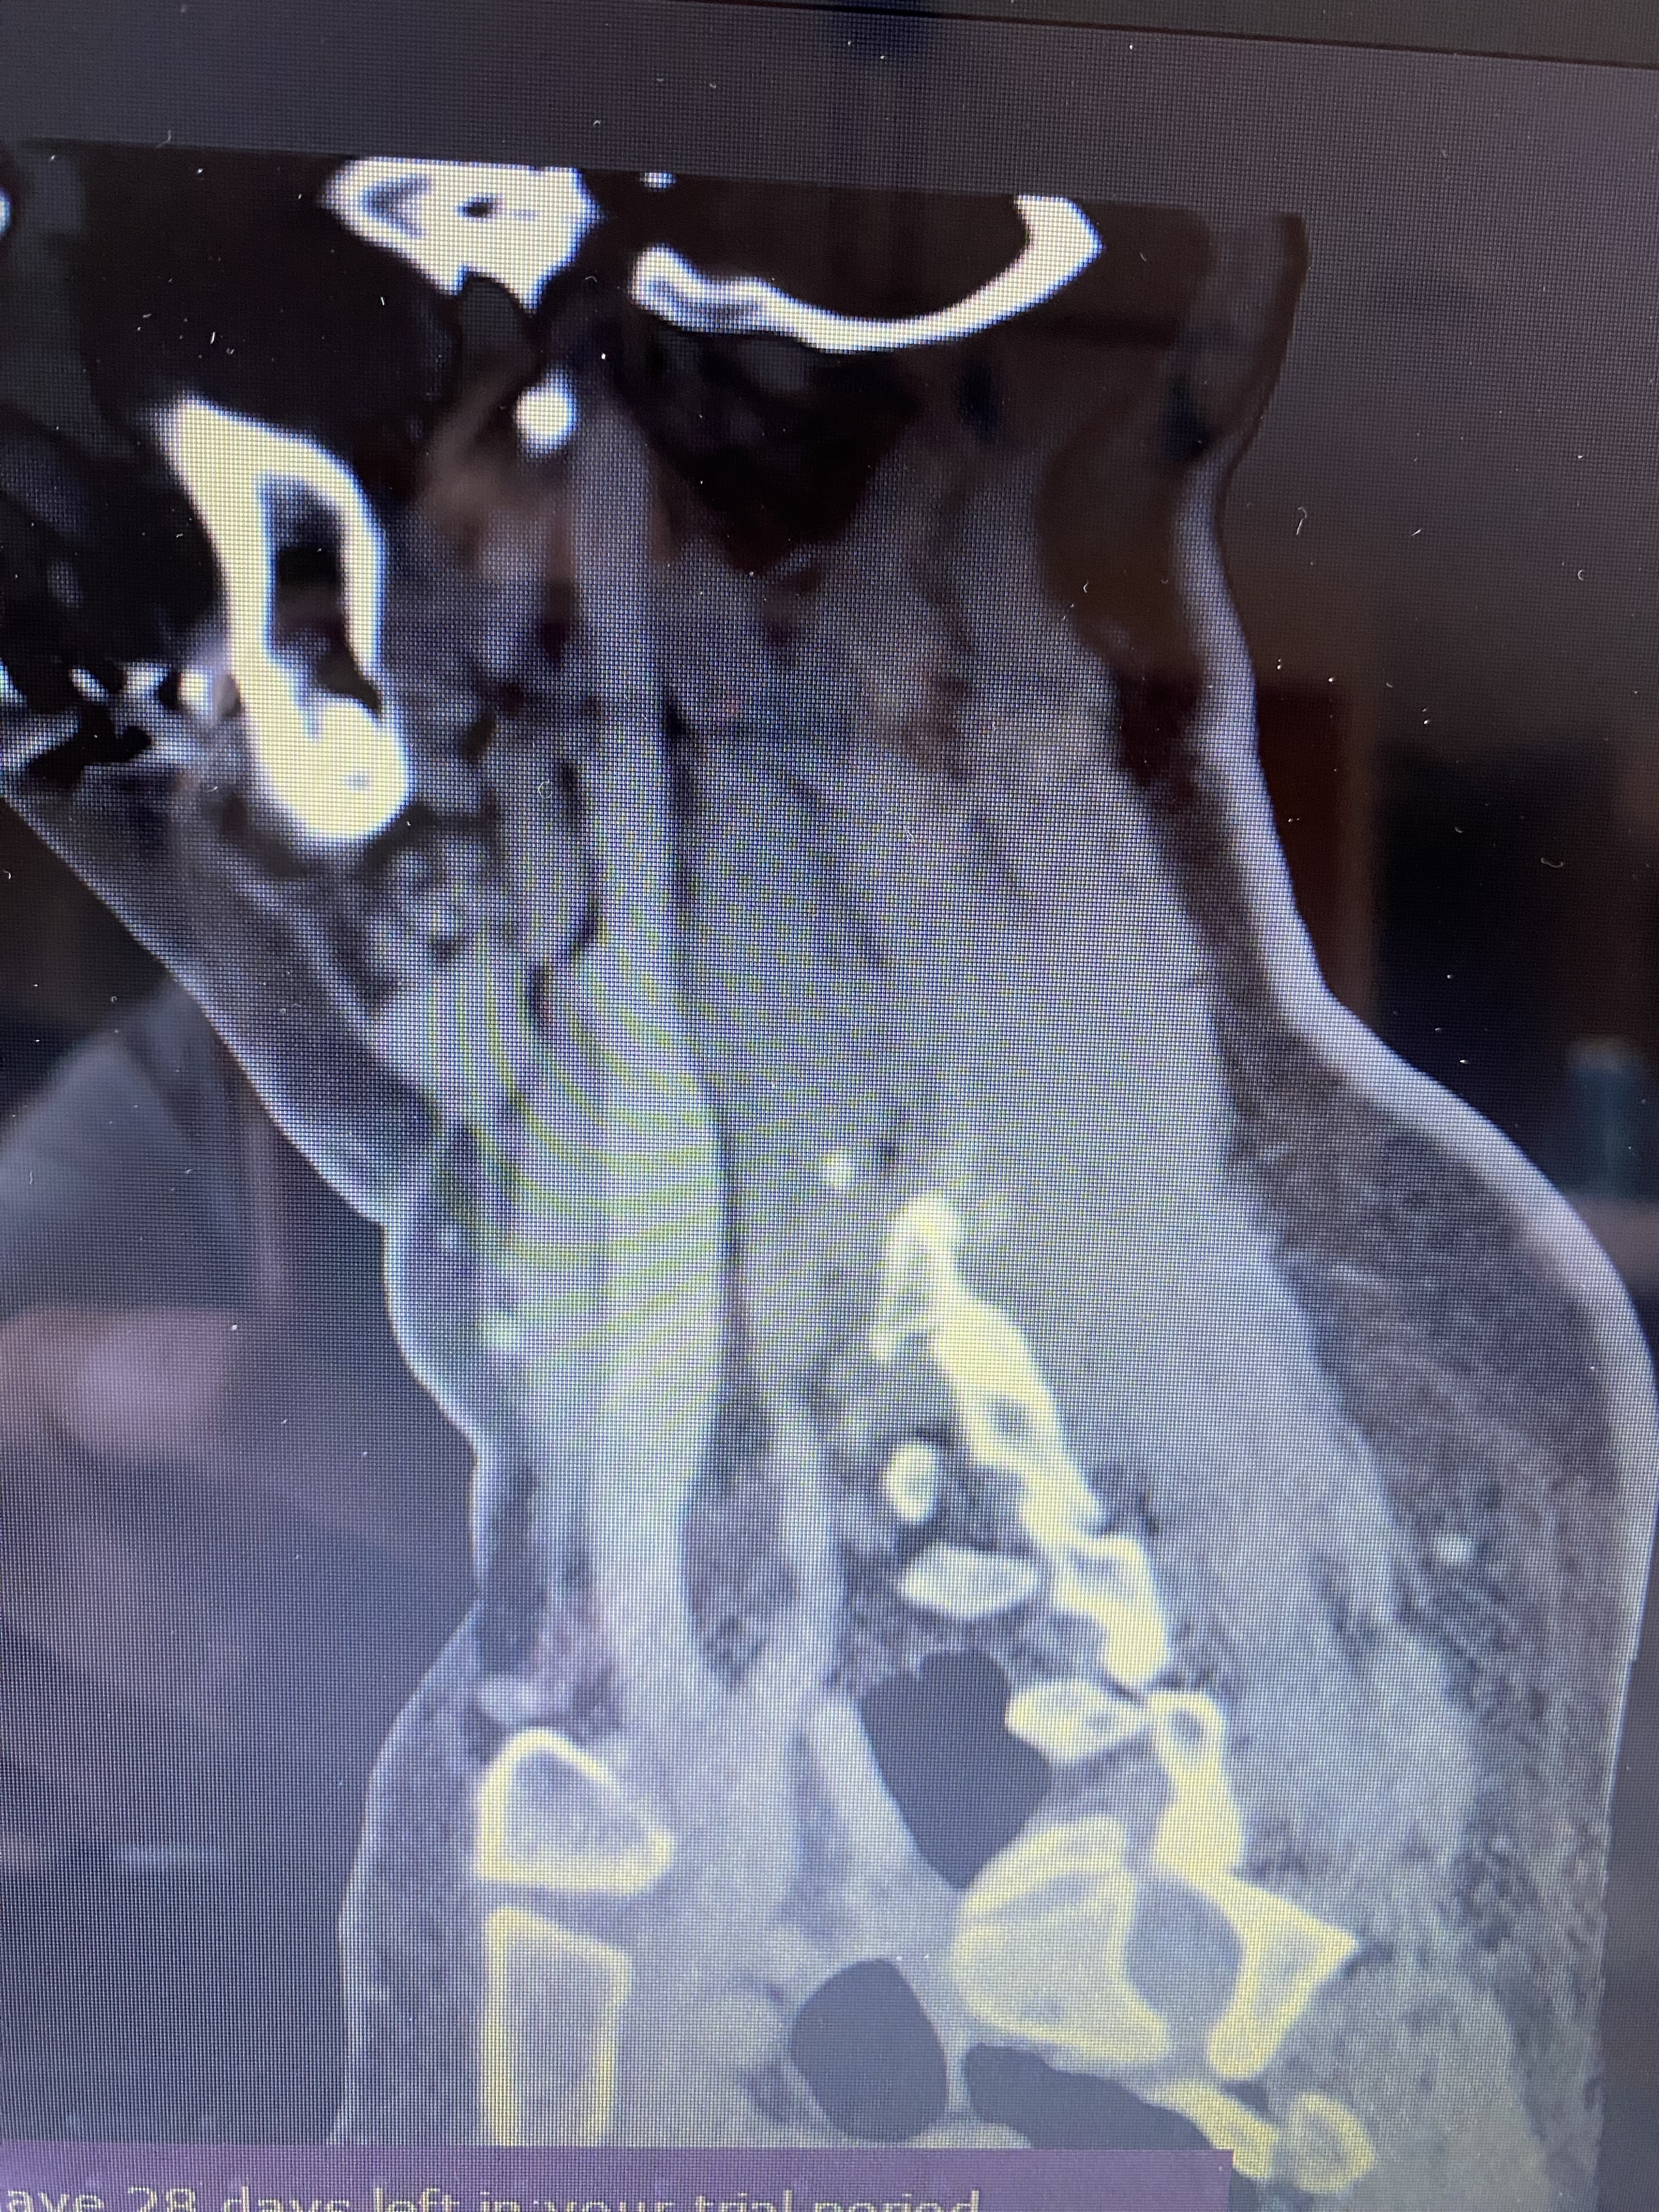

Finally got my images I’ll try to include them for you, Costantino thinks that doing the one side should be enough to relieve my remaining symptoms and he’s very positive about this as I’ve had improvement from my other two surgeries, half my left styloid removed and left trifecta for TOS, fingers crossed he is right.

@Millymay - Your right styloid is long! Getting your IJV decompressed & the styloid shortened, etc., will hopefully be answer to resolving your remaining symptoms. Your left styloid is notably very thick. Is it causing any IJV compression or only the right side?

I have compression on both sides, I also have allot more pain and numbness on the left side it had gone away initially with surgery but has come back again, I just had TOS surgery on the left also so I can see why he wants to start with the right, but I don’t think I’m going to get away with just the one surgery, but the surgeon is hopeful lol

I have a feeling the left is growing again, he did not remove very much on that first surgery